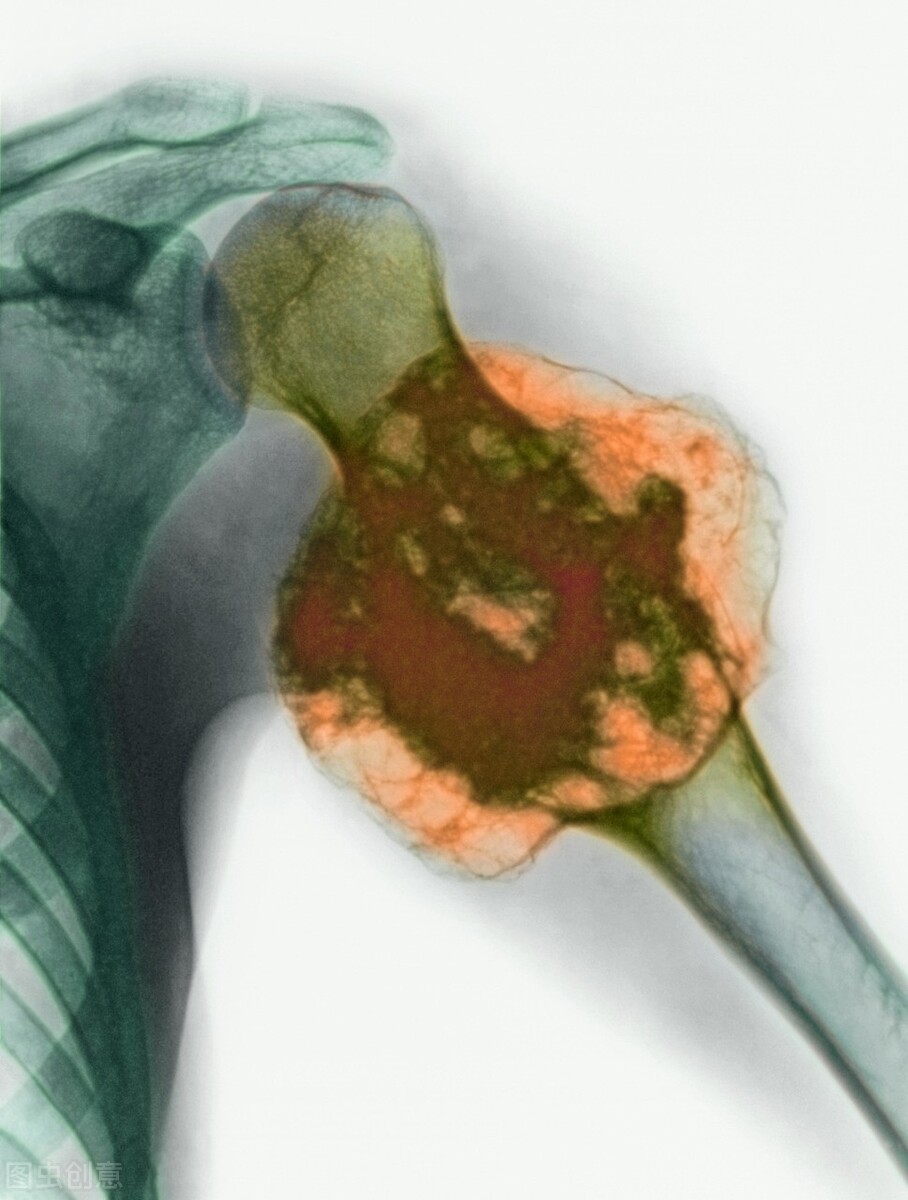

骨巨细胞瘤(giant cell tumor of bone, GCT)是良性、局部侵袭性肿瘤,由成片的卵圆形单核瘤细胞均匀分布于大的巨细胞样成骨细胞之间组成,占所有骨肿瘤的20%。好发年龄20~40岁。多见于股骨下端、胫骨上端、肱骨上端、桡骨远端。受累局部疼痛、肿胀、皮肤充血、静脉曲张,有压痛。

早期关节活动不受限,X线片显示溶骨性破坏位于长骨骨端偏心位,一侧皮质膨胀变薄,无骨膜反应,可有软组织阴影。病灶周围骨质清晰,多数无硬化反应骨,有时为筛孔样。多房肥皂泡样改变少见。骨巨细胞瘤生长活跃,侵袭性强,囊内刮除容易复发。

2%巨细胞瘤患者可发生远处转移,传统的病理分级已不能反映良恶性。骨巨细胞瘤多数是良性的,彻底的囊内切除应是首选的手术方法,骨水泥填充可获得临界切除的效果,复发率可降至10%~15%。骨巨细胞瘤恶变,骨端广泛破坏时,关节面有病理骨折时,应采用瘤段截除和关节功能重建。